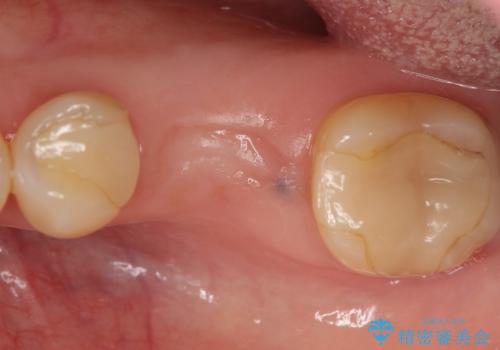

- 左下6の歯で咬むと痛みがあり、たまに膿も出てくるので診て欲しいといらっしゃった方の症例です。

被せ物を外したところ歯が割れており保存不可能だったため抜歯し、インプラントによる欠損補綴を行いました。